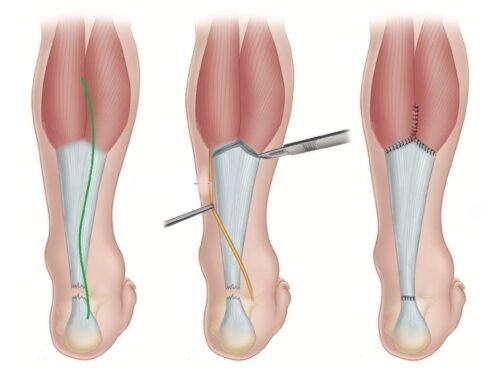

Тендинит Ахиллова сухожилия: симптомы и лечение

Раздел: Картинки на заметку